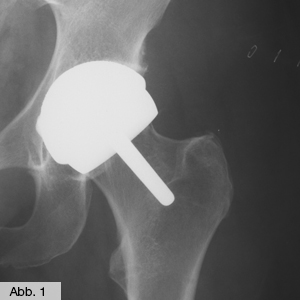

Bild Orthopädie Hüfte Oberflächenersatz

Kommt es mit Hilfe konservativer Maßnahmen nicht zum gewünschten Erfolg oder ist die Erkrankung bereits zu weit fortgeschritten, kann durch einen künstlichen Gelenkersatz Abhilfe geschaffen und Beweglichkeit sowie Schmerzfreiheit zurückgewonnen werden. Der Einsatz eines künstlichen Hüftgelenks erfolgt mit modernster Technologie (z.B. intraoperative Navigation). Neben den Routineverfahren mit zementierten und zementfreien Implantaten kommen auch spezielle knochensparende Prothesen für junge Patienten, Oberflächenersatz (Abb. 1) sowie Implantate zur Behandlung starker Deformitäten zur Anwendung. Wann immer möglich, werden die Kunstgelenke über minimal-invasive Techniken eingesetzt (s. EndoProthetikZentrum).

Je nach Profil des Patienten – Lebensalter, Körperbau, Knochenqualität, Lebensgewohnheiten/-aktivitäten – entscheiden wir individuell, welche Prothese eingesetzt wird. Oberflächenersatz und Kurzschaftprothese kommen als knochensparende Hüftimplantate vorzugsweise bei jungen Patienten zum Einsatz, bei denen im Laufe ihres Lebens in der Regel eine Wechseloperation erforderlich sein wird (nach ca. 20 bis 25 Jahren). Beim Oberflächenersatz (Abb. 1) werden im Gegensatz zur Vollprothese der Schenkelhals und Hüftkopf belassen und der arthrotisch veränderte Kopf lediglich mit einer Metallkappe überkront. Am Becken wird eine Hüftpfanne, vergleichbar mit der normalen Vollprothese, eingesetzt, so bleiben der natürliche Schenkelhals und der Kern des Hüftkopfes erhalten – als ausgewiesener Experte war Chefarzt Prof. Dr. Thomas Heß an der Entwicklung des Oberflächenersatzes "McMinn" beteiligt. Ein typisches Merkmal dieser Prothesen ist ein (ungefährlicher) Anstieg des Kobalt-Chrom-Spiegels im Blut, worüber der Patient informiert sein muss. Obwohl bei dieser Methode kaum Komplikationen auftreten, ist sie nicht für alle Patienten geeignet. So ist auch die Kurzschaftprothese (Abb. 2) auf jüngere und aktive Menschen mit einer guten Knochensubstanz zugeschnitten: Durch das verkürzte Prothesendesign bleibt ein größerer Teil des Oberschenkelknochens unberührt, dies schafft im Falle einer Wechseloperation gute Voraussetzungen für die sichere Verankerung einer Revisionsprothese. Bei älteren Patienten oder Patienten mit schlechterer Knochensubstanz kommt hingegen die Standardprothese (Abb. 3) zum Einsatz, die tiefer in den vorhandenen Knochen eingebracht und unter Umständen mit Knochenzement befestigt wird. Für Austauschoperationen stehen verschiedene modular aufgebaute Spezialprothesen zur Verfügung, mit denen Knochenverlust ausgeglichen werden kann. Alle verwendeten Prothesen bestehen aus hochwertigen und gewebefreundlichen Metalllegierungen (meist Titan). Noch wichtiger ist allerdings das Material der beweglichen Prothesenteile – hier werden meist hochabriebfeste Keramik oder spezielles hochvernetztes Polyäthylen verwendet.